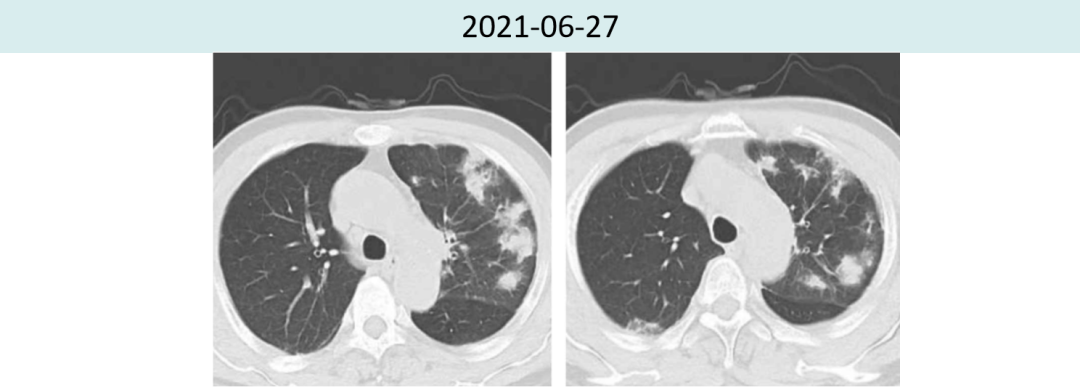

2021年6月27日抗感染9天后,复查胸部CT提示:两肺炎症较前无好转。

综上,排除感染性肺炎可能。

综合评估后,考虑发生2级免疫性肺炎。

2021年7月19日激素治疗3周后,胸部CT提示:两肺炎症较前明显好转,肿瘤疗效评价持续PR(4.5cm→1.6cm)。

图2.患者治疗前后肺炎情况对比